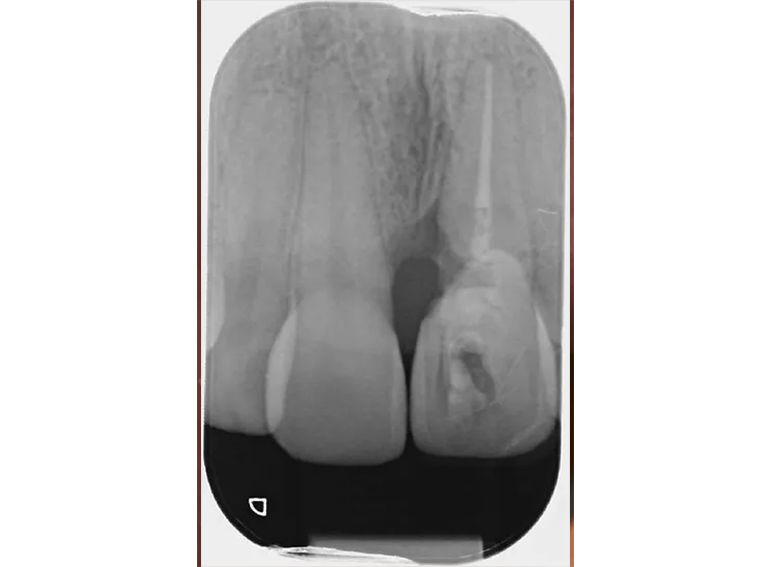

External cervical resorption extracted with a temporary adhesive bridge and final adhesive bridge.